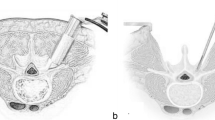

Finite element modeling of L4/5 TLIF procedures

The TLIF model was built as reported previously in the literature [19]. To simulate the processes of decompression and fusion, a left L4/5 facetectomy was performed; then, the entire nucleus pulposus, the left posterior part of the annulus fibrosus, and capsular and flavum ligaments were removed (Fig. 2A). The central region and the left posterior portion of the cartilage endplate at the L4/5 segment were removed to simulate the endplate preparation. A PEEK cage was placed on the anterior part of the L4/5 intervertebral space (Fig. 2B). Cancellous bone was implanted into the inner and outer spaces of the cage to fill the intervertebral space. The pedicle screw-based fixation system consisted of four screws (diameter, 6.5 mm; length, 45 mm) and two connecting rods (diameter, 5.5 mm; length, 58 mm) (Fig. 2C). The cage-bone graft, cage-endplate, bone graft-endplate, bone-screw, and screw-rod interfaces were assigned a “tie” constraint.